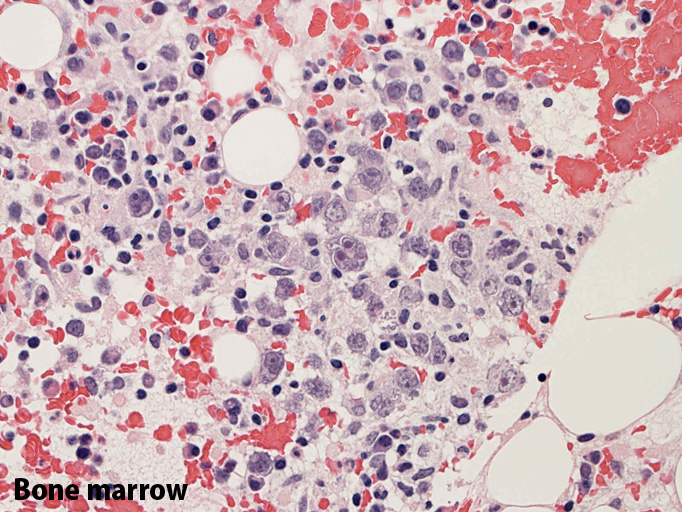

File not found: BM02_s.jpg File not found: BM03_s.jpg  骨髄;細動脈内のみに腫瘍細胞が認められた。類洞や髄内での増殖は見られなかった。

(骨髄穿刺吸引では発見できなかった原因のようです。骨髄生検で細動脈がとれないと診断に結びつかなかったでしょう。)